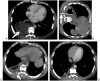

Infectious, traumatic, or neoplastic processes in the chest often result in fluid collections within the pleural, parenchymal, or mediastinal spaces. The same fundamental principles that guide drainages of the abdomen can be applied to the chest. This review discusses various pathologic conditions of the thorax that can result in the abnormal accumulation of fluid or air, and their management using image-guided methods.